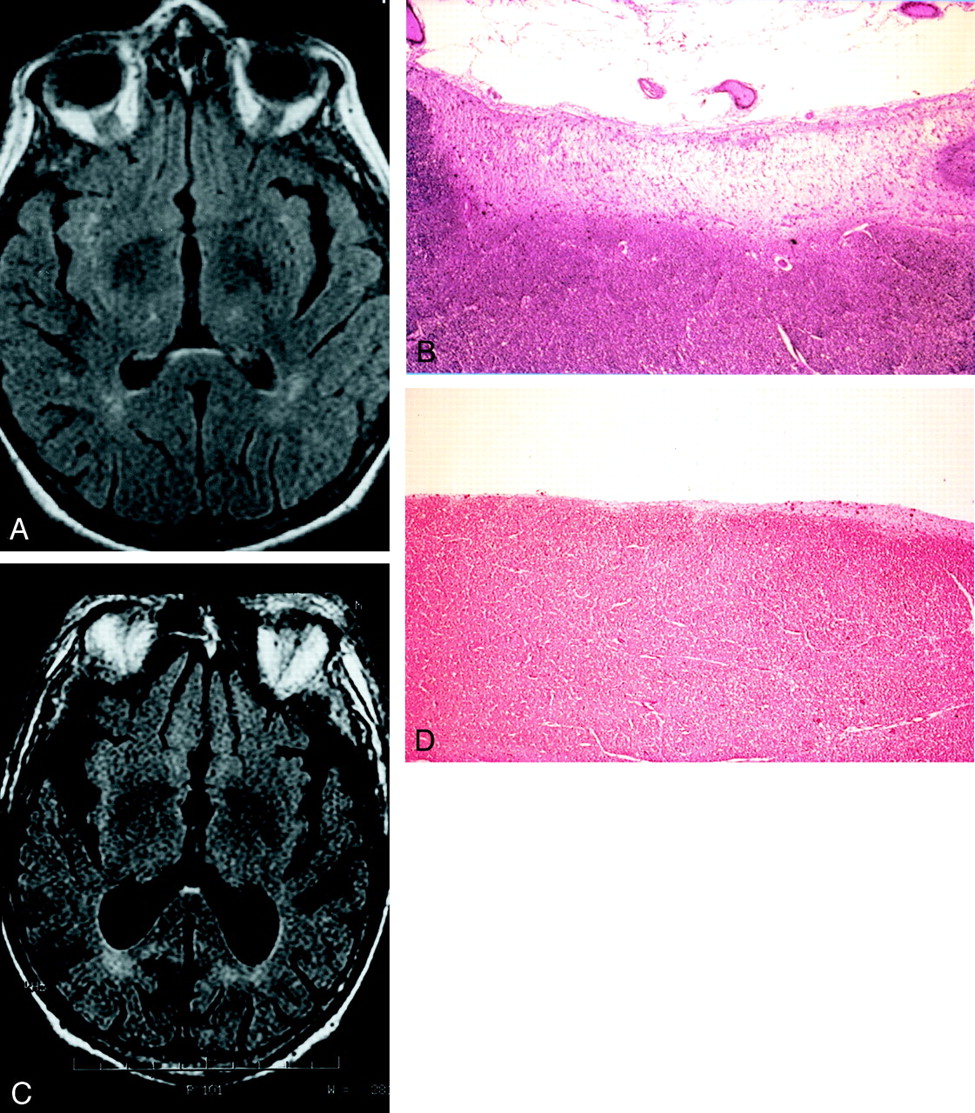

Case of a 67-year-old patient imaged to rule out aneurysm.

A, Axial and B, sagittal FLAIR MR images (10,000/156/1) show high signal intensity in the anterior subependymal region of the splenium of the corpus callosum, involving more than half the thickness (grade 2).

Two autopsy cases.

A, Axial FLAIR (10,000/156/1) image obtained in a 63-year-old man shows grade 1 signal intensity abnormality in the anterior subependymal region of the splenium.

B, Photomicrograph of histologic specimen of the splenium (same patient as in A) demonstrates a band of isomorphic gliosis (hematoxylin and eosin stain; original magnification, x60).

C, Axial FLAIR (10,000/156/1) image obtained in an 80-year-old man shows grade 1 signal intensity abnormality in the anterior subependymal region of the splenium.

D, Photomicrograph of histologic specimen of the splenium (same patient as in C) shows no gliosis (hematoxylin and eosin stain; original magnification, x60).